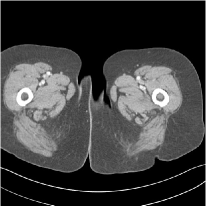

III.C.2. Simulation Framework, Reconstruction Results, and Comparisons

The synthesized low-dose clinical measurements are simulated from regular-dose images at a resolution of mm with a fan-beam CT geometry corresponding to a monoenergetic source at incident photon intensity . The sinograms are of size . The width of each detector column is mm, the source to detector distance is mm, and the source to rotation center distance is mm. We reconstruct images of size with the pixel size being mm mm.

We conducted experiments on one test slice used for parameter tuning (L067-slice 120) and four independent test slices (L109-slice 90, L192-slice90, L333-slice140, L506-slice 100) of the Mayo Clinic data. For PWLS-EP, we ran iterations using relaxed OS-LALM and set regularization parameter . We used the same as the phantom experiments for Algorithm 2. The process of selecting a general set of reconstruction parameters () for the Mayo Clinic test slices is identical to that for the XCAT phantom in Section III.B.2. The selected regularization parameter and the parameters that control the sparsity of the coefficient maps are for ST, , , , , for MARS2, , , , , , , for MARS3, , , , , , , , , , , for MARS5, and , , , , , , , , , , , , , , for MARS7, respectively.

Figs. 8, 9, 10, and 11 show the reconstructions of the four independent slices using the FBP, PWLS-EP, PWLS-ST, PWLS-MARS2, PWLS-MARS3, PWLS-MARS5, and PWLS-MARS7 schemes, respectively. Additional Mayo Clinic experimental results of the parameter tuning case (Fig. 15) are shown in the supplementary document. Table 1 lists the RMSE and SSIM values of reconstructions of the four independent test slices, with the best values bolded. Generally, the five and seven layer models provided the best RMSE and SSIM values. They outperform the single-layer model by HU in RMSE on average. However, the MARS5 and MARS7 models perform similarly. In order to strengthen the benefits of the multi-layer model, Table 2 lists the RMSE of the reconstructions in four different ROIs (shown in the reference of Fig. 11) with seven methods for slice 100 of patient L506. By observing the reconstructed images, we see that although the ST model achieves a cleaner reconstruction result than FBP and PWLS-EP, it still sacrifices some sharpness of the central region and suffers from loss of details. The deeper models have a somewhat more positive effect in terms of maintaining subtle features, which is clearly more essential to clinical diagnosis. Furthermore, as we will discuss later, after considerable parameter tuning, we found that the information contained in residual maps is gradually decreased with the number of layers, eventually vanishing at some layer, which suggests that very deep unsupervised models might not offer significantly better image quality.